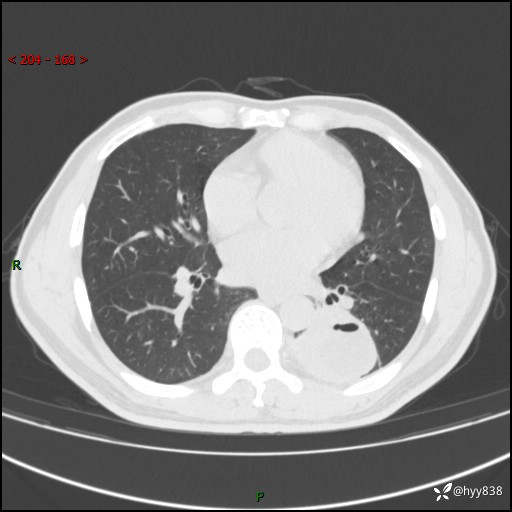

57岁/男,间断痰中带血1月余。纤支镜没有取到东西,穿刺轻松搞定---结果公布~

现病史:患者1月余前无明显诱因出现咯血症状,为痰中带血,量不大,伴轻度咳嗽,2024-3-26于当地市中医医院行胸部CT示:左肺下叶占位性病变。现患者仍有咳嗽不适,无发热乏力,无腹泻、便秘,无咳嗽,无头晕、无双下肢水肿等伴随症状,未行特殊治疗,今日患者再次出现咯血症状。患者为求进一步诊治,遂入我院,门诊以“肺脓肿”收入我科。 患者病程中,精神食欲可,二便正常,体力体重较前变化不明显。

胸部CT平扫

增强